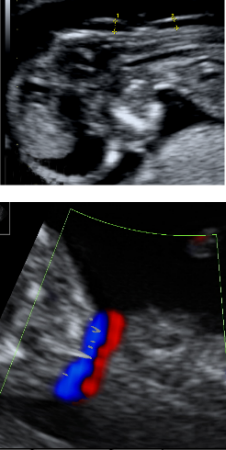

Diagnóstico ultrassonográfico:

- Múltiplos nódulos ecogênicos no coração (rabdomioma, usualmente > 20 semanas) e cérebro (tubérculos corticais e nódulos subependimais, usualmente > 30 semanas).

- Diagnóstico diferencial: fibroma cardíaco, que é único, grande e geralmente associado a derrame pericárdico.

- Esclerose tuberosa é vista em 50% dos casos de rabdomioma ( nos outros 50% dos casos o tumor cardíaco é isolado). Quando há múltiplos rabdomiomas, o risco de esclerose tuberosa é > 90%.